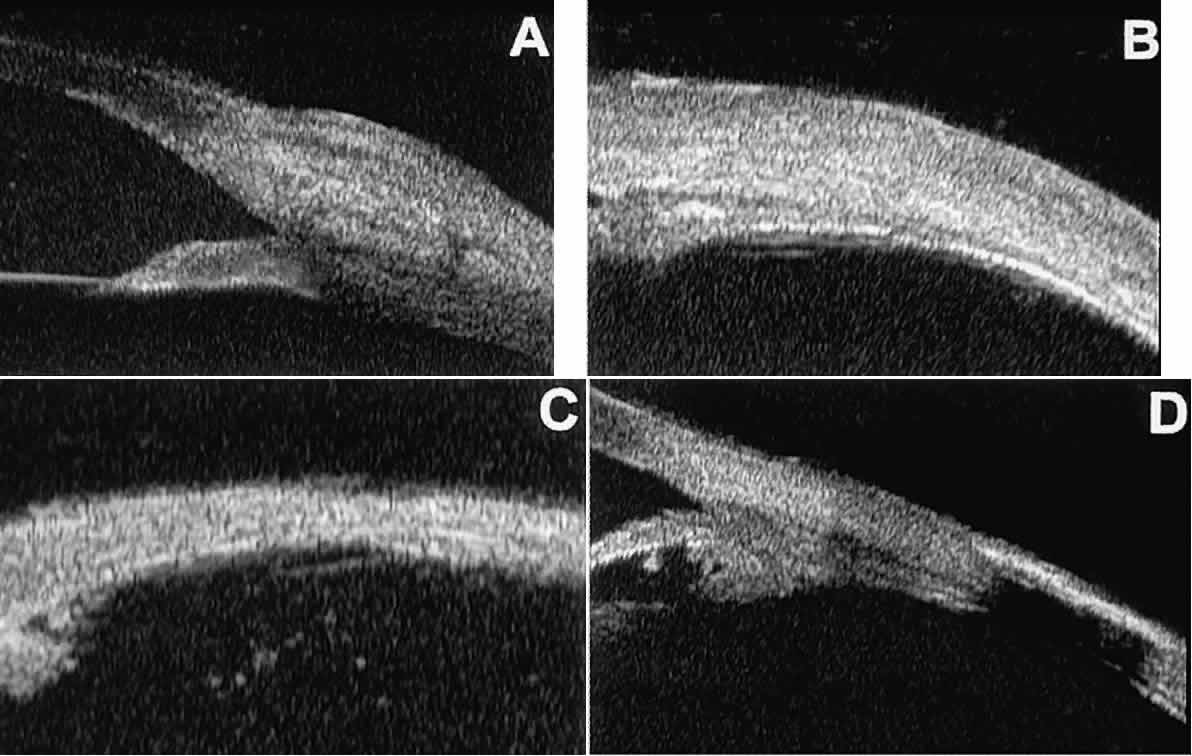

In eyes with a narrow angle, UBM shows the extent of angle closure, reveals

the depth of the anterior and posterior chambers, and identifies

pathologic processes pushing the lens and iris forward (Fig. 11).2–4,8 UBM has been able to differentiate between primary angle closure (i.e., cases of angle closure without additional pathology responsible for the

anterior lens-iris displacement [see Fig. 11A] and secondary angle closure due to processes such as lens swelling

and dislocation (see Fig. 11B), massive hemorrhagic retinal detachment pushing the lens and iris anteriorly (see Fig. 11C), and multiple neuroepithelial cysts of the iridociliary sulcus (see Fig. 11D).  Fig. 11. Angle configuration in eyes with angle-closure glaucoma. A. Primary angle-closure glaucoma with anterior displacement of lens and

iris. B. Angle closure secondary to swollen, cataractous lens (phakomorphic angle

closure). C. Angle closure secondary to massive hemorrhagic retinal detachment; the

subretinal blood is evident in the lower right corner of the photograph. D. Angle closure secondary to multiple peripheral iris cysts. Fig. 11. Angle configuration in eyes with angle-closure glaucoma. A. Primary angle-closure glaucoma with anterior displacement of lens and

iris. B. Angle closure secondary to swollen, cataractous lens (phakomorphic angle

closure). C. Angle closure secondary to massive hemorrhagic retinal detachment; the

subretinal blood is evident in the lower right corner of the photograph. D. Angle closure secondary to multiple peripheral iris cysts.

|